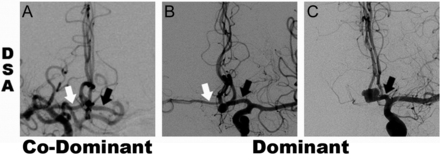

A1 vessel dominance of either anterior cerebral artery trunk supplying both pericallosal arteries was determined by the combined anatomic and flow dilution method illustrated in Fig 1 as previously shown.3 This allowed division of the AcomA aneurysm group into 2 groups: A1 codominant and A1 dominant. In the A1 codominant group, there was no clear dominance of the inflow contribution of one A1 segment over the other. If flow data were not available, the A1 codominance was determined if diameter of A1 (large) ≤ 2 × A1 (small). In the A1 dominant group, there was clearly more contribution of flow from one A1 segment to the distal A2 segments than the contralateral A1 segment, or no detectable inflow contribution from the contralateral A1 segment. If flow data were not available, A1 dominance was classified when A1 (large) ≥ 2 × A1 (small) or A1 (small) was not apparent or detectable on the available imaging.

DSA studies showing examples of A1 segment categories with white and black arrows indicating right and left A1, respectively, for codominant (A) and dominant (B and C) configurations. Panels B and C demonstrate A1 dominant cases with diminutive and absent contralateral A1 segments, respectively.